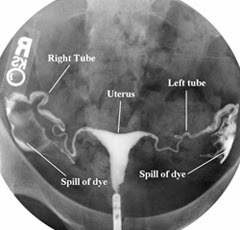

A normal, healthy woman’s pictures would look like the below. You can see both fallopian tubes fill with dye and the dye spill out into the uterus.

![]() |

| Normal HSG Test Pictures |